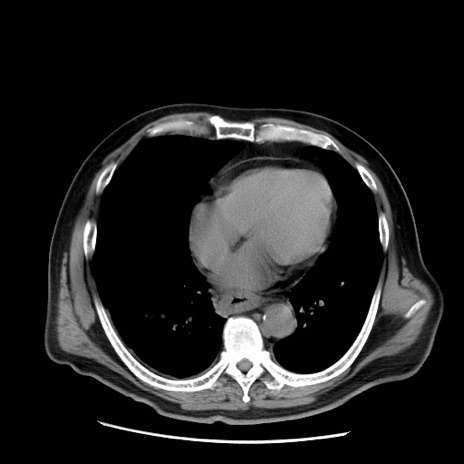

症例20(横断像)

【症例】 60歳代男性

【主訴】 腹部膨満、嘔吐

【現病歴】5日前頃より倦怠感を認め食事量減少し4日前の朝嘔吐、食事摂取困難となった。 3日前近医受診し点滴施行され整腸剤などを処方された。 当日他院を受診し、腹部膨満著明、炎症反応の上昇(CRP10.8、WBC11200)あり、紹介受診となる。

【身体所見】 意識JCS1 受け答えがはっきりしないBP 111/57mHg、 P 67bpm、、BT35.2°C、SpO2 97%(RA)、 腹部:膨隆、打診で鼓音あり、全体的に圧痛有り、腸蠕動音(-)、反跳痛ははっきりせず。

【データ】WBC 11400、CRP 14.20